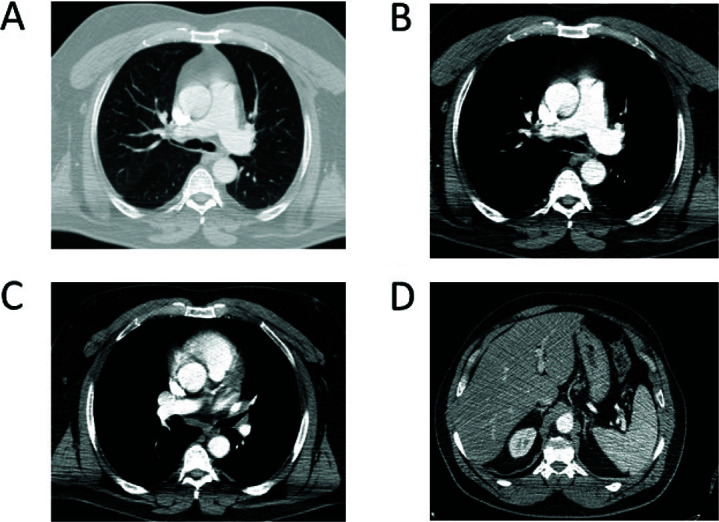

The advent of immunotherapy, and in particular the use of immune-checkpoint inhibitors, has profoundly revolutionized the treatment of different cancers, including lung cancer. The use of immune-checkpoint inhibitors has prolonged survival in lung cancer with a strong benefit in a significant percentage of patients with non-small-cell lung cancer. Here, a clinical case of a patient who, despite testing negative for PD-L1, displayed a sustained complete response to immunotherapy treatment in advanced metastatic non-small-cell lung cancer is presented. Additionally, recent findings concerning the application of immunotherapy in this context are reviewed.

Abstract Image